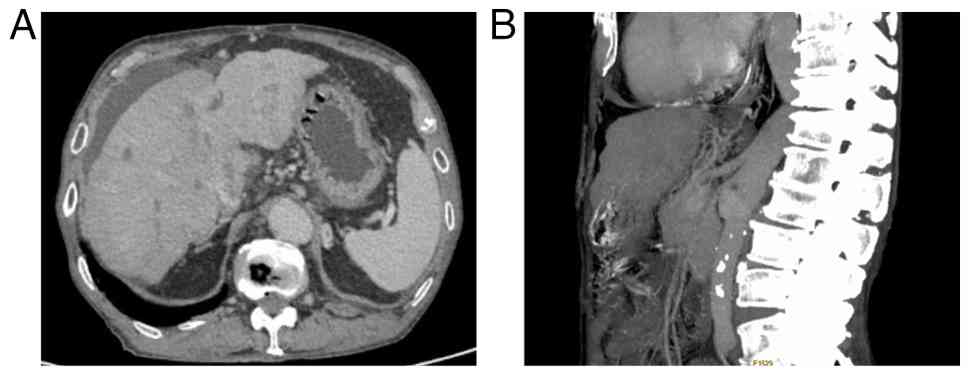

In June 2024, a 74-year-old man was admitted to Huai'an Hospital Affiliated to Yangzhou University and The Fifth People's Hospital of Huai'an (Jiangsu, China) with symptoms of coughing, hemoptysis, decreased appetite and abdominal distension. The patient had a history of chronic obstructive pulmonary disease spanning over 20 years. Computed tomography (CT) identified a 12.3-cm soft-tissue mass in the left lower lobe of the lung, with multiple metastatic lesions noted in the liver (Fig. 1). A biopsy of the lung lesion under CT control was performed. Tissues were fixed in 10% neutral formalin solution at room temperature for 24 h, then dehydrated and embedded in paraffin. The tissues were sliced into 5-µm thick sections. Immunohistochemical analysis was performed using the EnVision two-step method. Both primary and secondary antibodies were ready-to-use antibodies purchased from Henan Celnovte Biotechnology Co., Ltd. The following antibodies were employed: CK5/6 (clone C6H1/C1C8; catalog no. CCM-0983), p40 (clone C3B4; catalog no. CPM-0133), p53 (clone C2H10; catalog no. CPM-0142) and Ki-67 (clone C3G4; catalog no. CKM-0032). All staining was performed using an automated immunohistochemical staining machine (catalog no. CNT360-M2; Henan Celnovte Biotechnology Co., Ltd.), according to the manufacturer's instructions. All section observations and image acquisition were performed using a light microscope (ECLIPSE Ci-S; Nikon Corporation). Immunohistochemical analysis of the tissue sample revealed positive expression of CK5/6, p53 and p40, and the Ki-67 index was 30% (Fig. 2). Based on clinical presentation, imaging studies and pathological findings, the patient was diagnosed with primary lung squamous cell carcinoma. The patient refused a liver biopsy and programmed death ligand 1 testing. The patient was diagnosed with squamous cell carcinoma of the left lower lung lobe and liver metastasis, cT4N3M1c, clinical stage IVB, according to the American Joint Committee on Cancer 8th edition (13). The patient received intravenous sintilimab (200 mg on day 1) and albumin-bound paclitaxel (200 mg on day 1 and 100 mg on day 8) plus cisplatin (30 mg on days 1–3) of each 21-day cycle for 4 cycles. In October 2024, the patient showed a significant reduction in measurable lesions with regard to both the primary tumor and liver metastasis. The mass in the lower lobe of the left lung decreased from 12.3 to 8.4 cm in diameter, while the largest liver metastasis shrank from 3.8 to 1.5 cm in diameter, with some liver metastases disappearing (Fig. 3). Following the aforementioned four cycles of sintilimab and albumin-bound paclitaxel plus cisplatin, the patient continued maintenance therapy with sintilimab (200 mg on day 1 of each 21-day cycle). Tumor status was assessed every 6 to 8 weeks. The assessment included CT scans of the chest, abdomen and pelvis. In June 2025, CT demonstrated a nodular contour of the liver with capsular retraction, mild ascites, and esophageal and gastric varices (Fig. 4). The patient had no history of alcohol consumption. Laboratory tests indicated negative or normal results for all causes of liver disease, including serological tests for hepatitis B and C, and serological tests for autoimmune conditions. The patient refused to undergo a liver biopsy. The patient's alanine aminotransferase level was 57 U/l (normal range, 9–50 U/l), aspartate aminotransferase was 55 U/l (normal range, 15–40 U/l), γ-glutamyl transferase was 185 U/l (normal range, 15–40 U/l), total bilirubin was 27.9 µmol/l (normal range, <26 µmol/l) and albumin was 29.4 g/l (normal range, 40–55 g/l). The patient underwent abdominal paracentesis, with large-volume drainage of ascites, diuretic therapy and infusion of human albumin (once daily, 10 g per dose) as part of active treatment. Over the next 2 months, the Eastern Cooperative Oncology Group (http://ecog-acrin.org/resources/ecog-performance-status/) performance status gradually worsened. In August 2025, the patient ultimately succumbed to hepatic failure.

Computed tomography scans

demonstrating (A) a nodular contour of the liver with capsular

retraction, mild ascites, and (B) esophageal and gastric

varices.

Figure 4.

Computed tomography scans demonstrating (A) a nodular contour of the liver with capsular retraction, mild ascites, and (B) esophageal and gastric varices.